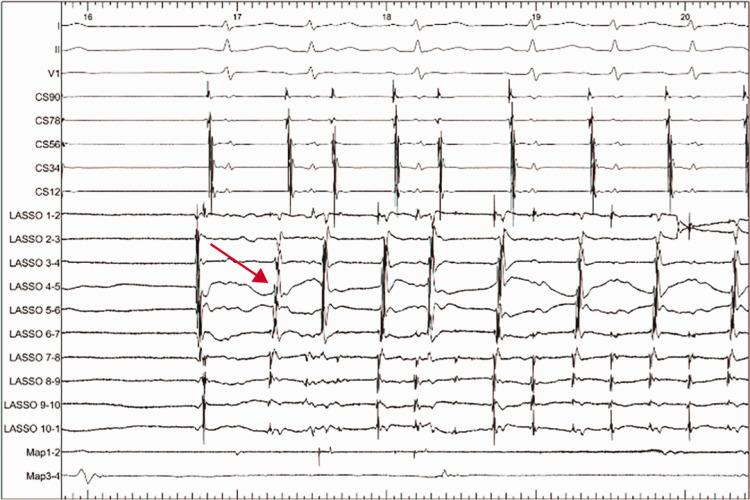

This prospective cohort study comprised 107 patients with PAF. The patients were divided into the FMR and non-FMR groups. FMR was assessed by Doppler echocardiography before index ablation. All patients initially underwent circumferential pulmonary vein isolation (CPVI) and were followed up for 12 months after ablation. PAF, atrial tachycardia, or atrial flutter served as the endpoint indicator.

The median duration of PAF was 24 (3-60) months. Binary logistic univariate and multivariate analyses showed that FMR was not a risk factor for recurrence of catheter ablation for PAF (hazard ratio=0.758, 95% confidence interval: 0.191-3.004; hazard ratio=0.665, 95% confidence interval: 0.134-3.300, respectively). Kaplan-Meier analysis showed no significant difference in the recurrence rate between the groups. Fifteen (15/107, 14%) cases of PAF were triggered by the pulmonary vein. Three (3/107, 2.8%) cases of PAF were triggered by the superior vena cava.